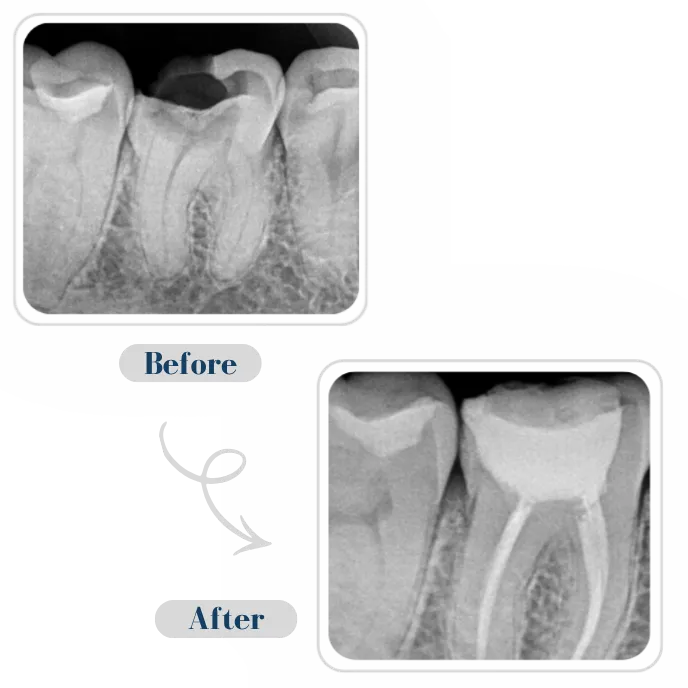

Our Root Canal 3 Step Process

Examination & X-ray

Removal of infection & cleaning

Sealing the tooth to prevent reinfection

- Root Canal Treatment — Pain-free procedures, natural preservation